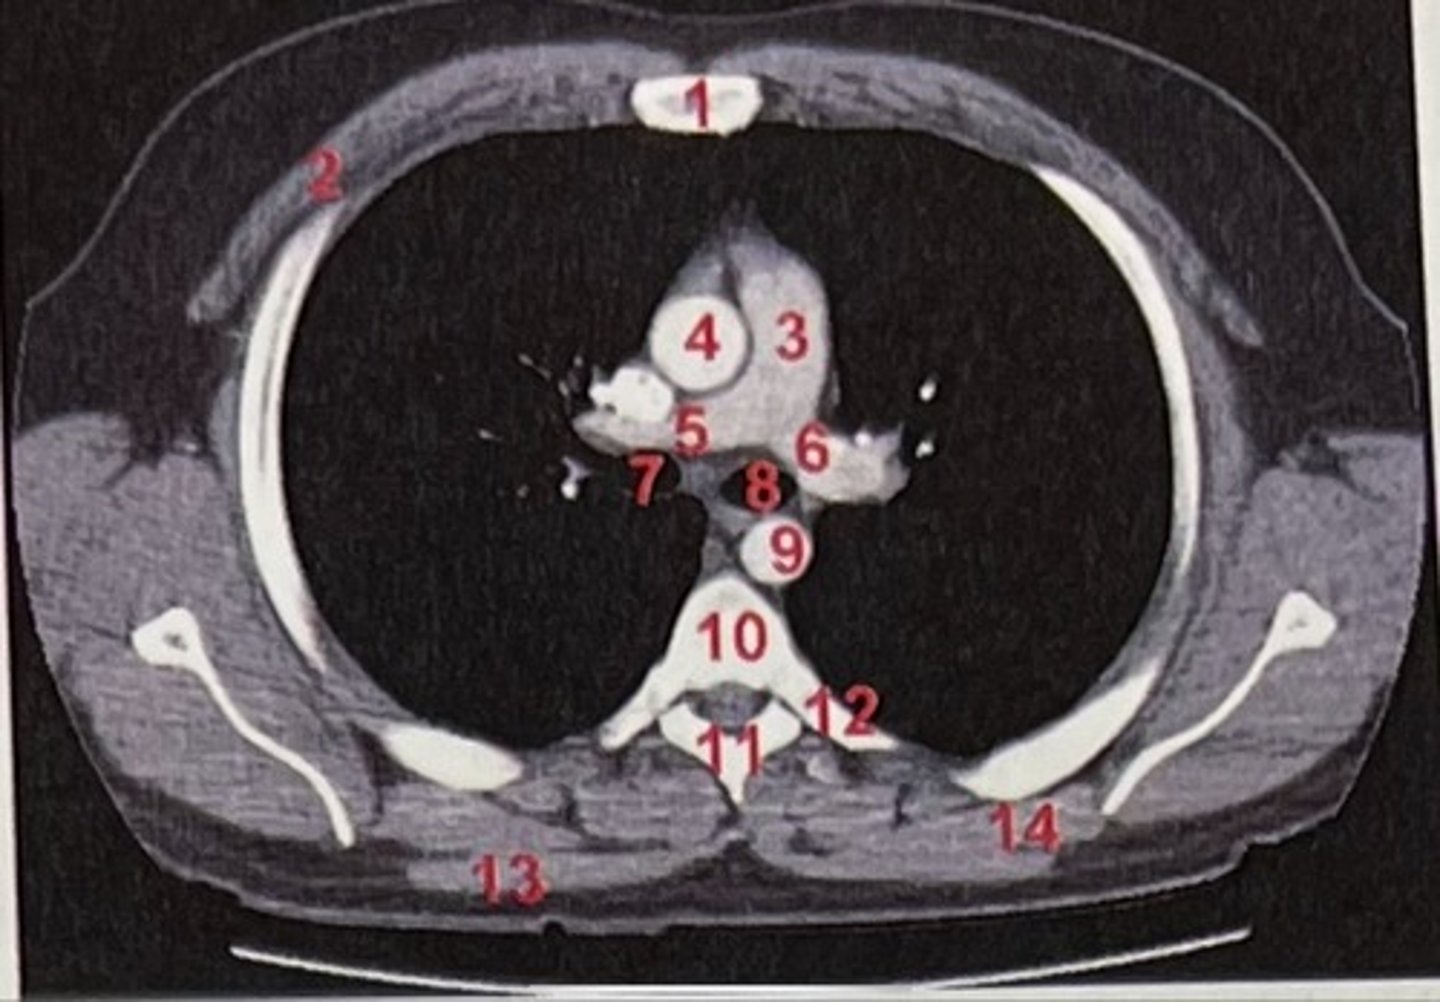

Sternum

What is 1

pectoralis major

What is 2

Pulmonary trunk

What is 3

Right and left pulmonary arteries

What is 5 and 6

Ascending aorta

What is 4

right primary bronchus, left primary bronchus

What is 7 and 8

Descending aorta

What is 9

Rhomboid major

What is 14